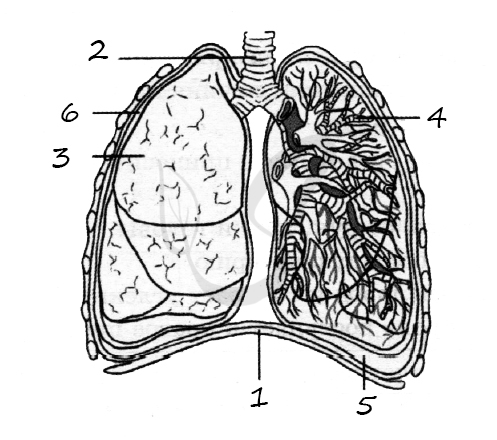

Анатомические изображения сегментов легких различных животных

Раздел: Другие животные